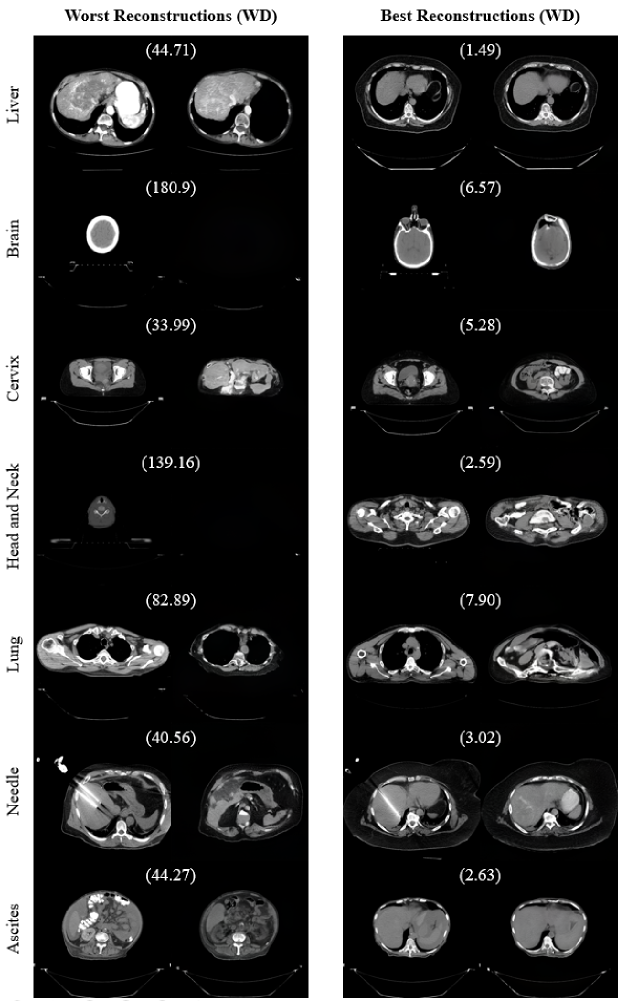

The generative adversarial network (GAN)-based OOD detection paradigm detected non-liver images with high AUROCs (Table 1). The GAN seemed to model non-liver images by manipulating abdominal features (Figure 1), which resulted in large reconstruction errors. The liver images that were classified as OOD often contained underrepresented artifacts. For example, in the worst reconstruction of an in-distribution liver image in Figure 1, the network failed to model adjacent organs that had a high amount of contrast.

Our paradigm was also able to detect liver images with abnormalities (Table 1). The GAN was completely unable to reconstruct needles and ascites (Figure 1). This is a promising result because segmentation models often fail on images that contain such artifacts [9]. Because the GAN is unable to reconstruct uncommon attributes, we will be able to better detect these variations in future work. We will be able to alert clinicians to these abnormalities, protecting against automation bias.

Refer to caption

Figure 1: The best and worst reconstructions for each dataset (according the WD). For each pair, the left image is the original and the right image is the reconstruction. The number in parentheses is the WD between the pair.